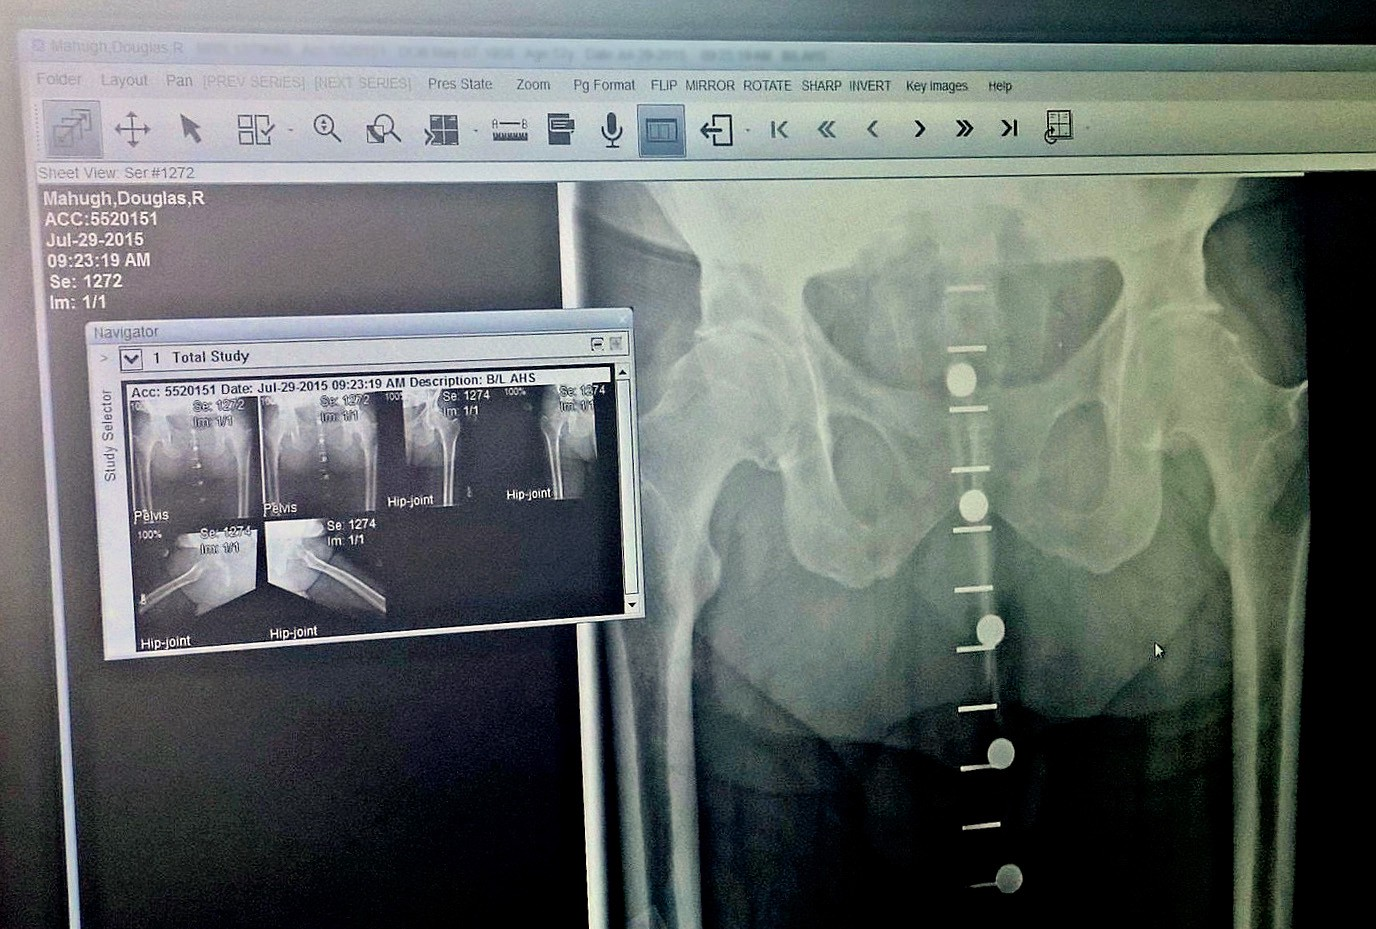

My appointment finally came on July 29, and after an examination and x-rays his diagnosis was a mouthful of big words: “End-stage osteoarthritis of both hips secondary to femoral acetabular impingement, manifested by the classic anterosuperior cartilage loss. Articular cyst formation in the acetabulum, circumferential femoral head osteophytes, and acetabular osteophytes.”

End-stage didn’t sound good, and Dr. Bruckner showed me how the x-rays compared with those taken one year before. Most of the remaining cartilage in both hip joints had worn away in just one year. Another active year and my hips would be bone on bone, but that wasn’t likely to happen, because hip pain was preventing me from having an active year.